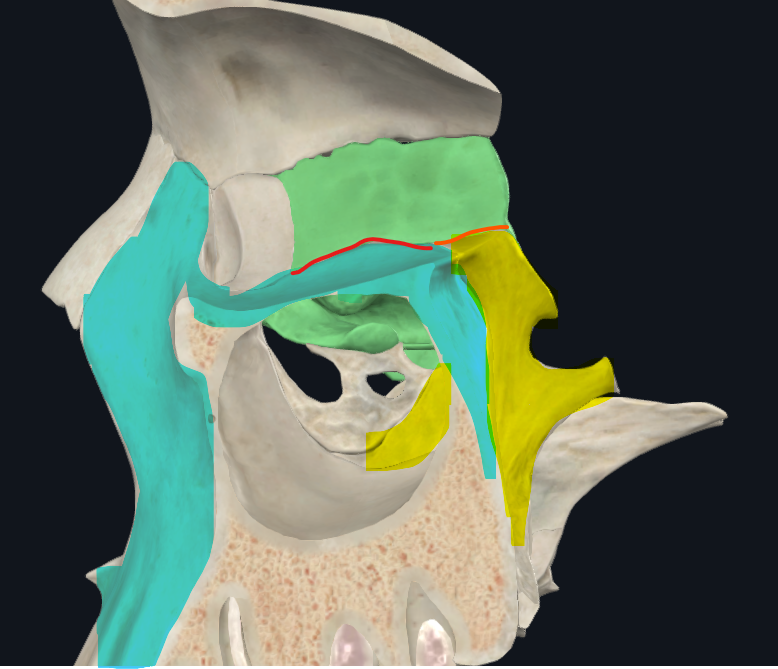

Lámina cribosa del etmoides

Lados se articulan con el frontal

Forma parte del piso de la fosa craneal anterior

Perforada por múltiples orificios, por eso el nombre de cribiforme

Dos apófisis alares que articulan con el frontal, creando el foramen cecum

Foramen Caecum

Llamado también Agujero Ciego

Agujeros etmoidales

Anterior y posterior

Laberintos Etmoidales

Forma cuboidea

Contiene los cornetes superiores y medios

Forma parte de la pared lateral de las fosas nasales

Contiene muchas cavidades neumáticas

Celdillas etmoidales, se dividen en anteriores y posteriores

Lámina papirácea en cara lateral